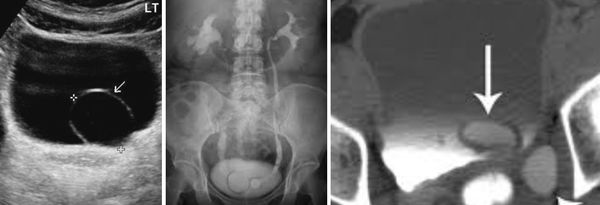

о Расширение правого мочеточника, сужение в месте перекреста с общими подвздошными артериями

о Расширение мочеточника до места входа в малый таз (где мочеточники перекрещиваются с подвздошными сосудами):

- Тазовый отдел мочеточника никогда не расширяется

о Возникает преимущественно на правой стороне (80-90%)

• Расширение мочеточника до места сдавливания (где мочеточник перекрещивается с подвздошными сосудами) с возвращением нормального калибра ниже:

о Цветовая допплерография позволяет отличить мочеточник от расширенных вен яичника

о Мочеточник должен вернуться к нормальному диаметру ниже входа в малый таз; отсутствие данного явления служит сильным основанием для подозрения на патологическую обструкцию:

- В некоторых случаях, когда есть подозрение на наличие камня в дистальном отделе мочеточника, могут использоваться трансвагинальный и трансректальный доступы для лучшего исследования дистального отдела мочеточника

- Артефакт «свечения» на цветовой допплерографии позволяет обнаружить небольшие камни в труднодоступных участках